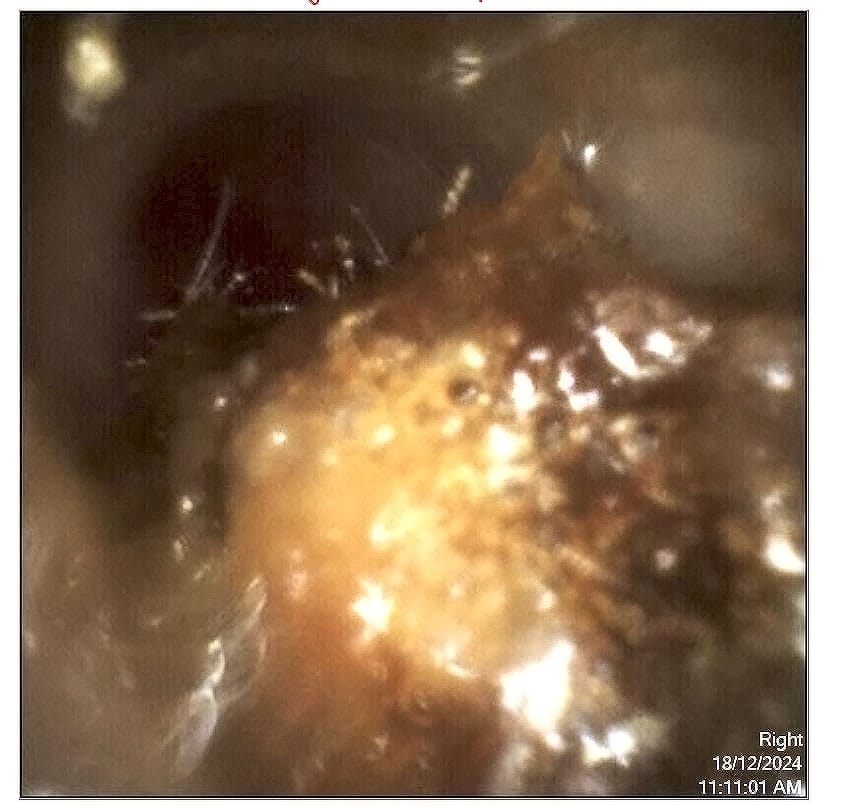

Microsuction uses a tiny vacuum attached to a thin probe, guided by either a microscope or video-otoscope, so we can see exactly what we’re doing, magnified! Think of it like a miniature vacuum cleaner for your ear canal. The audiologist watches the entire process through magnification, making real-time adjustments as the wax comes out.

The key difference comes down to visibility and control. With microsuction, we’re watching everything unfold. With syringing, the practitioner works somewhat blind, relying on water pressure to do the work.

You’ll sit in a comfortable chair. We’ll look in your ear first using an otoscope or a video camera to assess what we’re dealing with, and we’ll show you on screen if you’re curious.

The speculum (a slight funnel shape) holds your canal open. It feels like something sitting in your ear because it is. You’ll hear the suction activate: a rushing sound, sometimes with crackling or popping as wax pieces come loose. Some people find it surprisingly loud. This is normal and not damaging to your hearing.